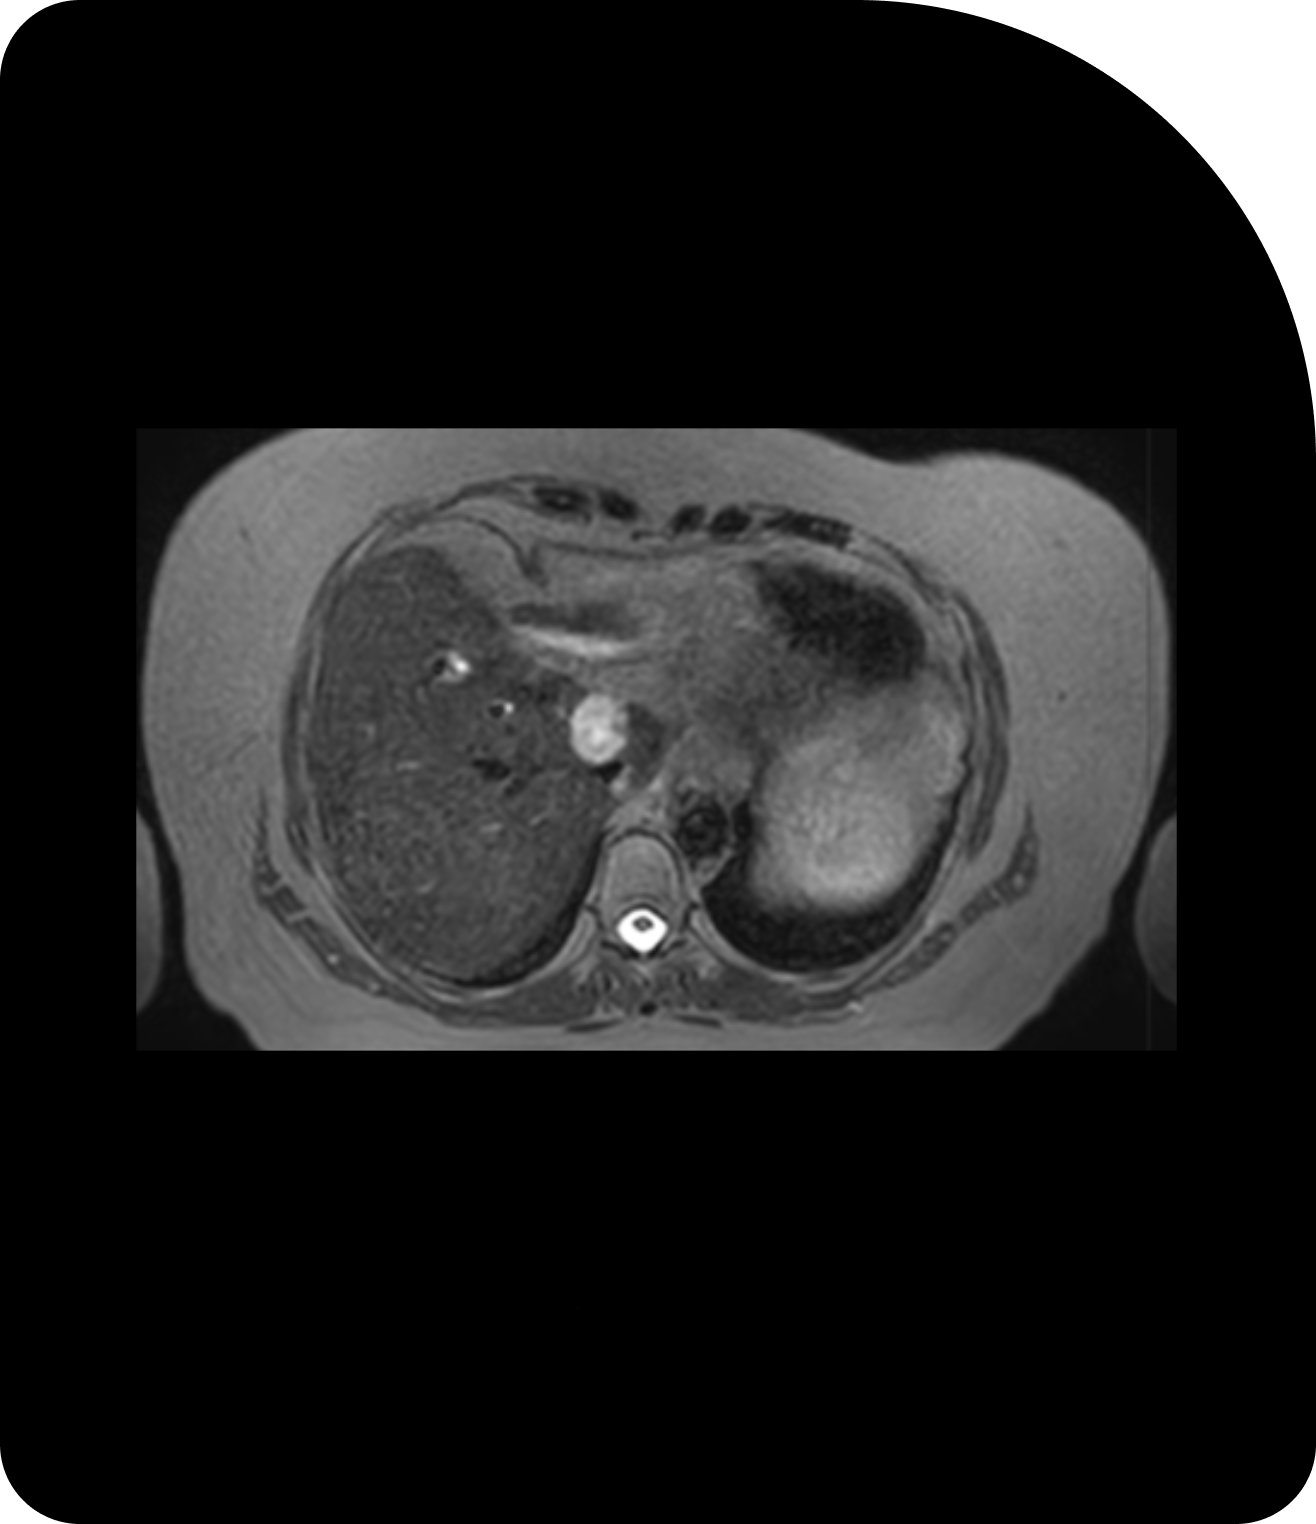

Des images plus claires signifient un ciblage plus précis. Comparez la tomodensitométrie (TDM), la tomodensitométrie volumique à faisceau conique (CBCT) et l’imagerie par résonance magnétique (IRM) pour constater la différence.

IRM

Le contraste supérieur des tissus mous révèle des détails plus fins pour une radiothérapie adaptative précise.

L’imagerie par résonance magnétique (IRM) offre un contraste inégalé des tissus mous, ce qui la rend particulièrement utile pour les tumeurs situées à proximité d’organes critiques tels que le pancréas ou la prostate. L’IRM permet également une imagerie en temps réel pendant le traitement, ouvrant la voie à des innovations telles que le suivi et la synchronisation en temps réel.